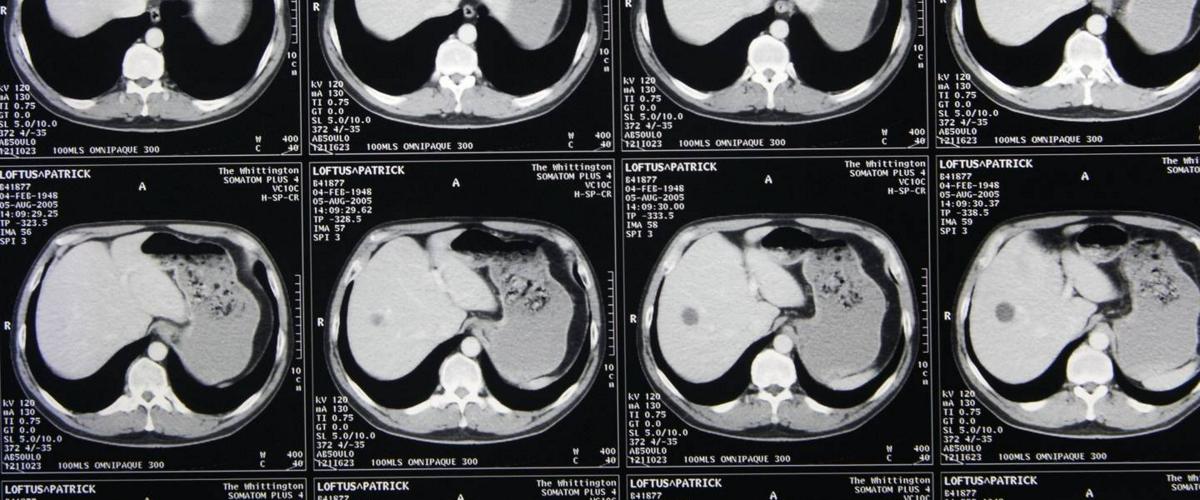

Как сообщает EurekAlert, искусственный интеллект под названием PatchFCN анализирует снимки компьютерной томографии мозга пациентов на предмет мельчайших кровоизлияний. В его основе — сверточная нейросеть, для тренировки которой достаточно относительно небольшого количества образцов. В данном случае использовалось всего 4396 изображений, однако все они были тщательно промаркированы, что обеспечило высокую эффективность обучения.

Проверка показала, что алгоритм обнаруживает следы кровоизлияния в мозг всего за секунду. Нейросеть видит даже небольшие отклонения, которые легко могут скрыться от взора специалиста-человека, и классифицирует их в зависимости от размера и расположения. Количество ложных срабатываний при этом невелико.